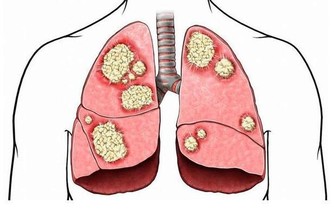

- 頸椎骨刺在刺激和壓迫頸背神經根時,會引發心前區疼痛、胸悶、氣短等症狀。